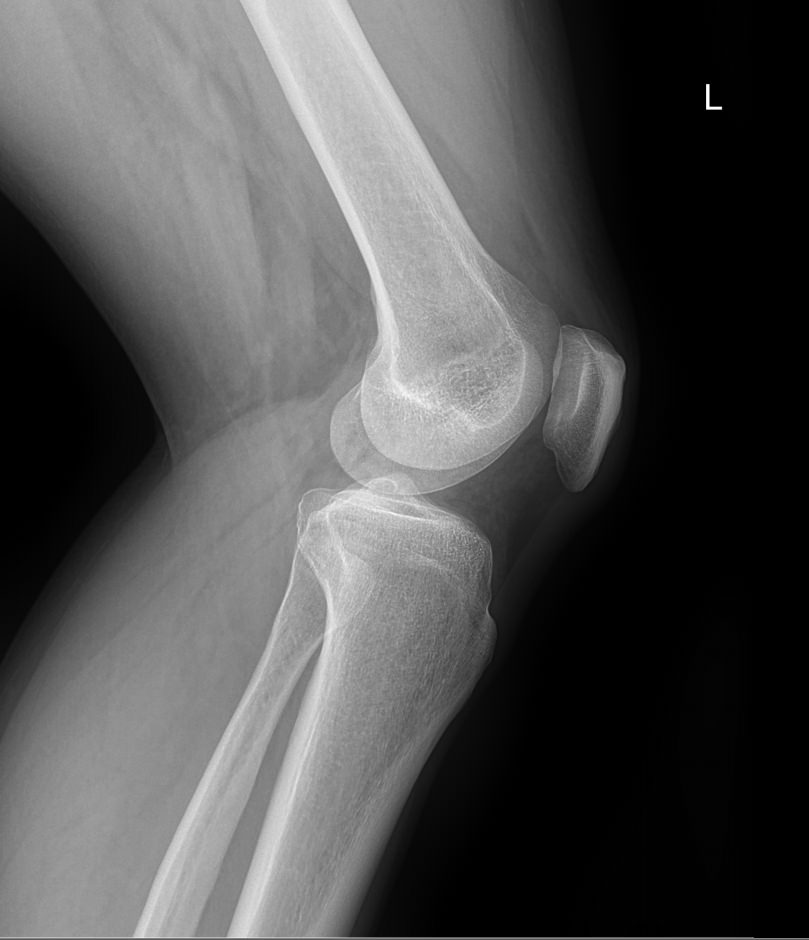

Что покажет рентген обоих коленных суставов в одной проекции

В протоколе у каждого сустава описывается:

• Состояние мягких тканей;

• Суставная щель ― в норме, расширена, сужена, затемнена, имеет дополнительные включения;

• Состояние суставных  поверхностей и их соответствие друг другу ― несоответствие говорит о вывихе;

• Положение надколенника ― обычное или нет;

• Состояние костной ткани и надкостницы ― могут быть обнаружены участки разрежения, размягчения или других патологических процессов, а также свежие и сросшиеся переломы.